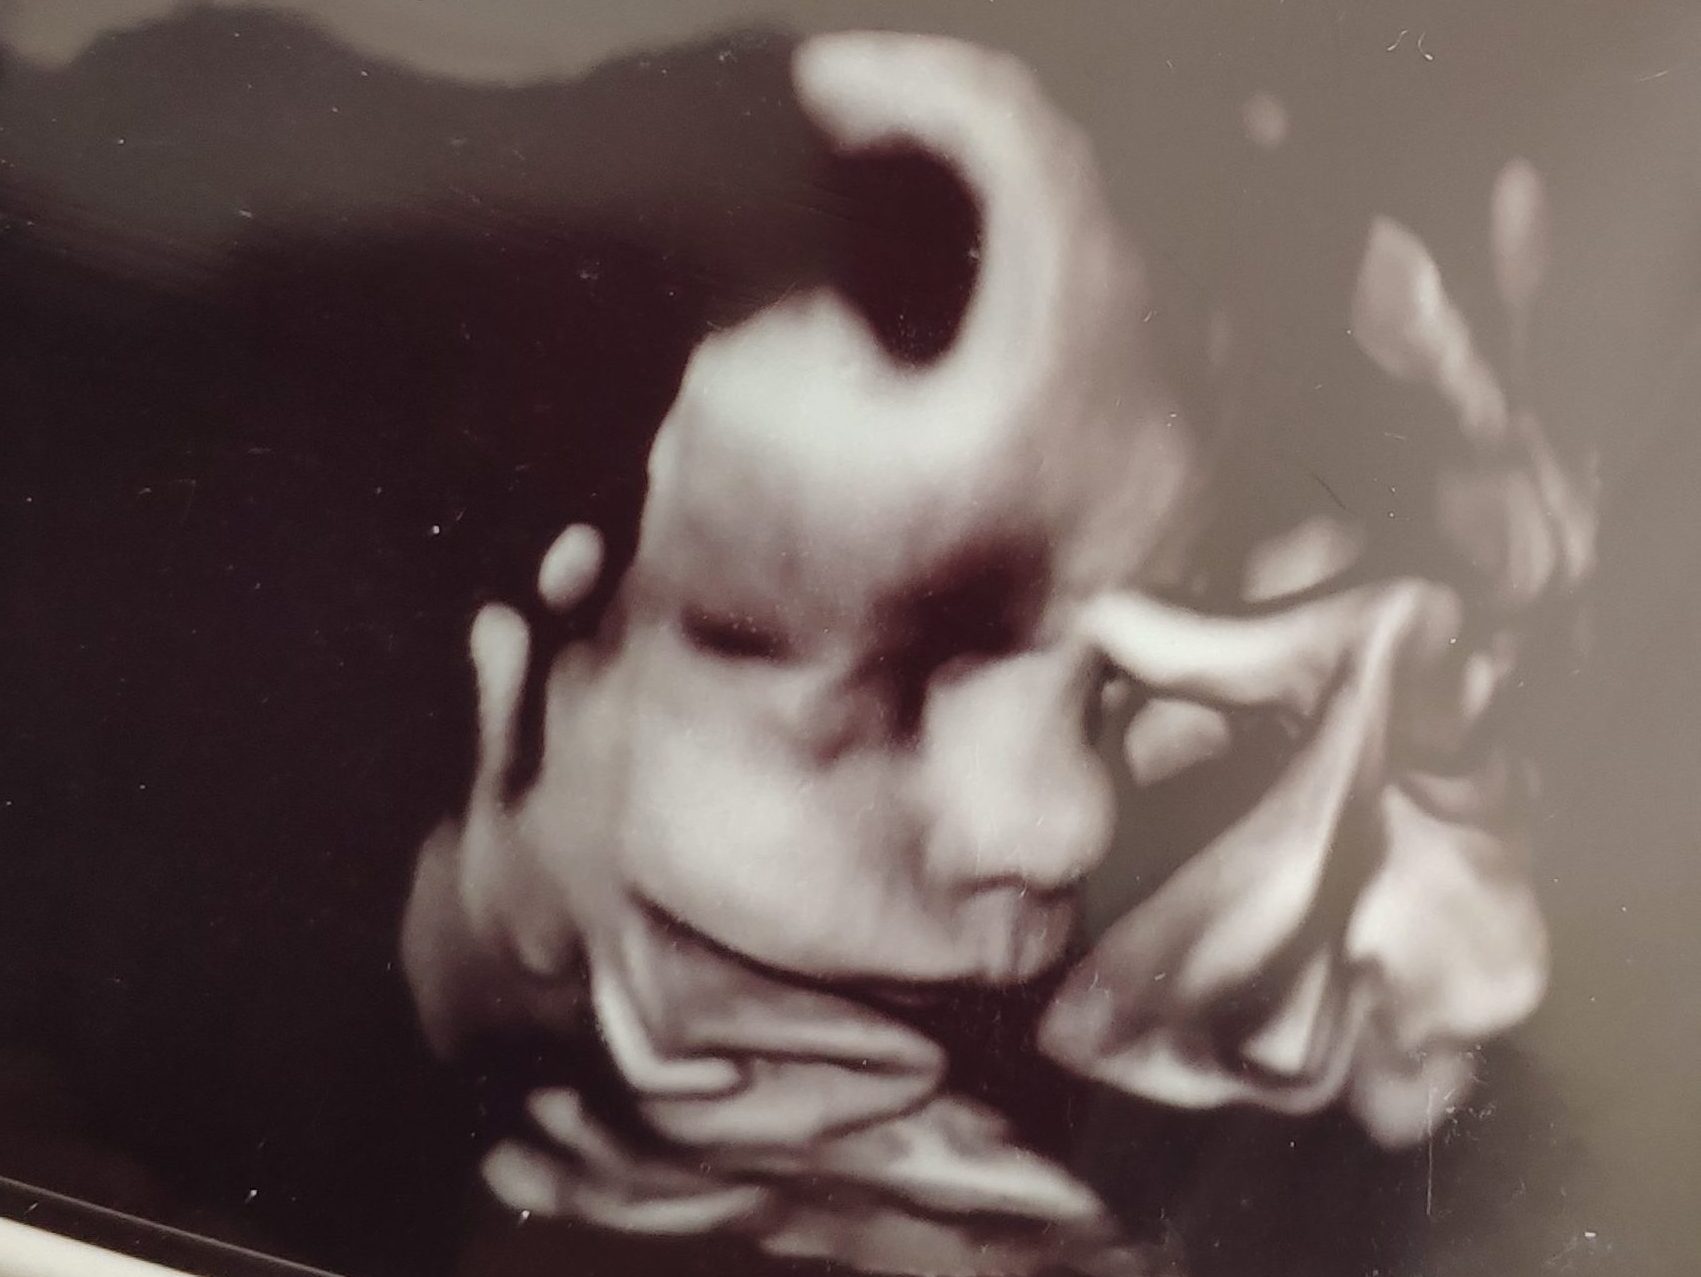

Davon abgesehen ist aber alles recht entspannt. Meine Symptome unterscheiden sich kaum von denen, die ich abseits meiner Schwangerschaft erlebt habe, und mein Optimismus ist ebenfalls intakt. Jetzt muss unsere Simone (nein, so wird sie nicht heißen) im Prinzip nur noch ein bisschen mehr Speck ansetzen. Von mir Bohnenstange kann sie da aber keine allzu große Hilfe erwarten. 😀